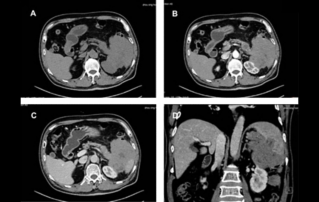

??? ???? ??? ?? ????? ??? ??? ?? ?????. ????? ? ??? 30mm?? 42mm?? ??? ? ??? ??? ??? ????? ?? ? ? ?? ? ?? ? ?? ??? ??? ??? ? ????. ?? R ? ???? ?? ?? ?? ?? ?? 7mm, ?? ?? 8mm???.

??? ?? ??? ??? ?? ??? ??? ??? ??????? ??????. ??? ??, ?? ???(colpoperineography), ?? ???(levatoroplasty), ?? ?????(TVT-O) ?? ??? ??? ?? ?? ????. ??? ??, ??-???? ??? ?? ??? ???? ?? ????? ?? ? ??? ?????? ??? ?? ? ????.